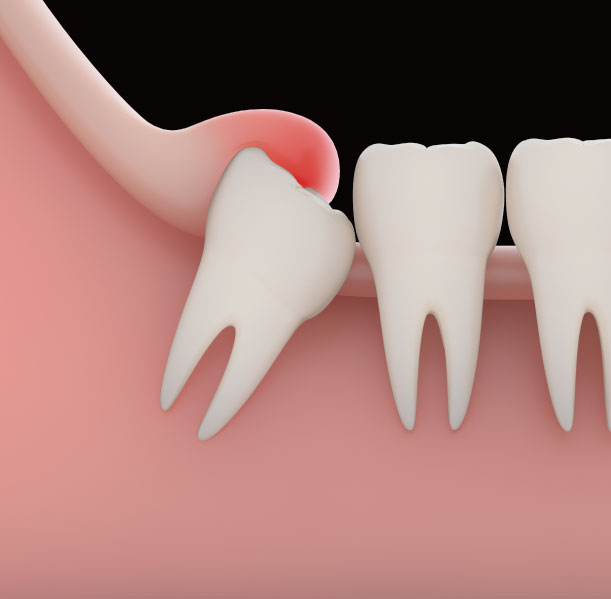

치과 치료를 하면 알 수 있는 것이 치아는 함부로 뽑지 않습니다. 정말 최대한 살려보고 그래도 안 되면 뽑아서 임플란트 등으로 빈자리를 채웁니다. 사랑니는 다른 치아들과 달리 발치를 해야 할 때도 있습니다. 잘 자란 사랑니는 특별한 문제를 일으키지 않아 뽑지 않아도 됩니다. 하지만 대부분의 사랑니는 말썽을 부립니다. 출혈, 염증, 통증 및 악취, 충치 들 여러 가지 문제를 일으킬 확률이 높기 때문에 뽑아야 합니다.